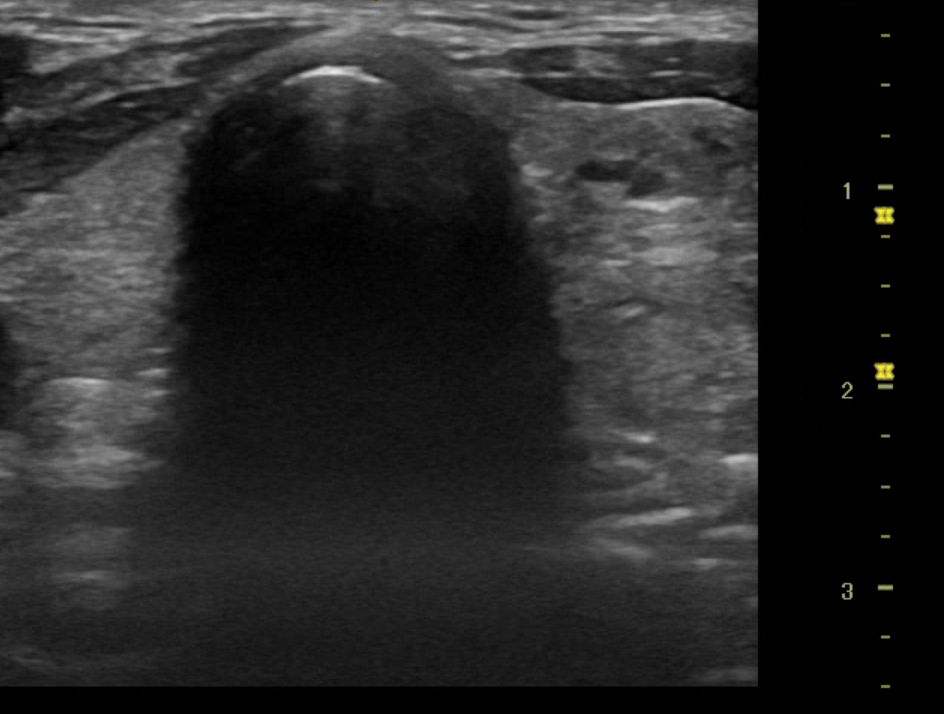

Se realizó ecografía en servicio de urgencias el cual encontramos los siguientes hallazgos:

Nódulo en polo inferior de lóbulo izquierdo de aproximadamente 2.08 X 1.47 x 3.63 cm de características de morfologías: con longitud mas alto que ancho, se observa trabéculas heterogéneas, visualizacion de leve vascularización sin evidencias de adenopatías colindantes, no se aprecia efecto masa en estructuras colindantes.